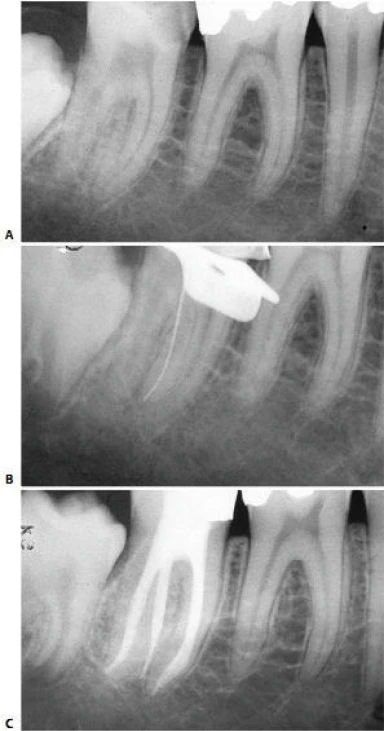

Ống xa thường có hướng khá thẳng, ngoại trừ hầu hết phần chóp thì thường nghiêng xa (hình 11.117). Lý do vì sao cong về phía xa cũng dễ hiểu, nếu như biết rằng hàm dưới vẫn còn phát triển về phía gần khi răng đã hoàn thành việc đóng chóp. Chóp chân răng hình thành xung quanh một cuống mạch máu, vào một thời điểm nào đó cũng sẽ nghiêng theo chiều gần xa.

Điều quan trọng là phải biết ống tủy có cong và dùng dụng cụ nhỏ, uốn cong trước. Một dụng cụ thẳng với kích thước không phù hợp sẽ bị cản trở bởi thành ngoài của chỗ cong, tạo cảm giác như dụng cụ đã đến tiếp xúc với chỗ thắt ở phía chóp hoặc chỗ nối cement ngà. Một dụng cụ nhỏ, uốn cong trước thì lại có thể dễ dàng vượt qua được đoạn cong ở phía chóp.

Hình 11.117. A. Phim trươc điều trị: ống tủy được điều trị bởi bột nhão iodoformic  B. Làm cong file 8: dễ dàng qua chỗ cong của ống tủy  C. Phim sau điều trị. D. Phim 2 năm sau. Chỗ cuối của vị trí trám bít ống tủy cách đỉnh chóp ít nhất 3mm.